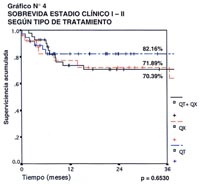

En el Gráfico N° 4, se aprecia la supervivencia acumulada a 36 meses, en aquellos pacientes con estadio clínico I y II de acuerdo al tipo de tratamiento recibido. Los pacientes que recibieron sólo quimioterapia, tuvieron una sobrevida a 3 años de 82.16%, los que recibieron sólo tratamiento quirúrgico alcanzaron el 71.89%, y aquellos que recibieron la modalidad combinada de quimioterapia y cirugía, llegaron al 70.39% en el mismo periodo de tiempo. No hubo diferencia con significancia estadística entre los tres grupos, con una p=0.6530, lo que sugiere que para los estadios clínicos I y II del Linfoma Gástrico, las tres modalidades de tratamiento en referencia, pueden alcanzar resultados semejantes.